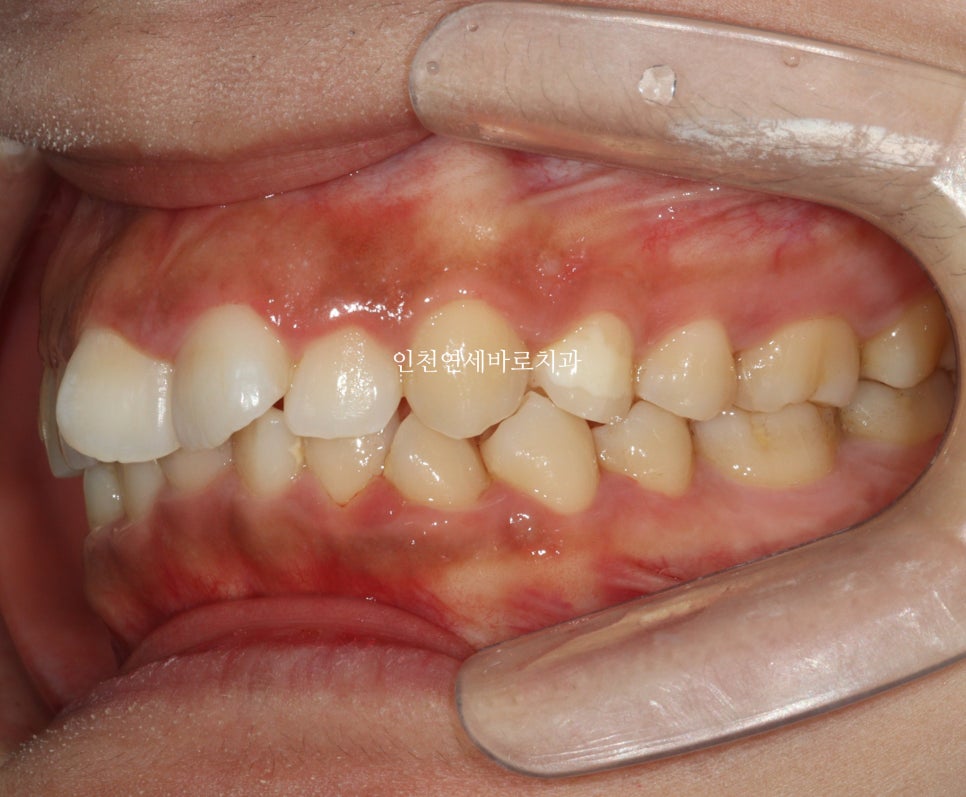

시작 후 약 4-5달 후 사진입니다.

위 사진이 7월에 재제작 했을 때 모습입니다.